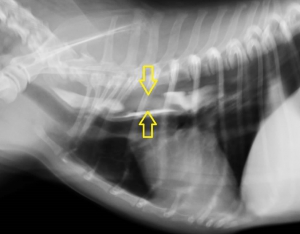

飼い主さんからの申告により、食道内異物はほぼ確実ですのでレントゲン撮影を胸部と腹部で行いました。

下の写真が胸部レントゲン写真です。黄色い矢印に挟まれた「白く細長い異物が見えると思います。この場所は胸部食道の心基底部(心臓の上)に近い部分で、食道閉塞を起こしやすい場所です。写真ではまた。食道閉塞に伴って飲み込んだ空気によって食道拡張がみられています。(右の赤い矢印の間)

ふつう、食道はレントゲン写真に写らないのですが、このわんちゃん、かなり苦しかったらしく大量の空気を飲んでおり、食道と胃に空気が入っています。このため、飲みこんだ空気が「造影剤」となって、異物が「空気造影」されており、幸いにもレントゲン写真で異物の存在が明らかになりました。